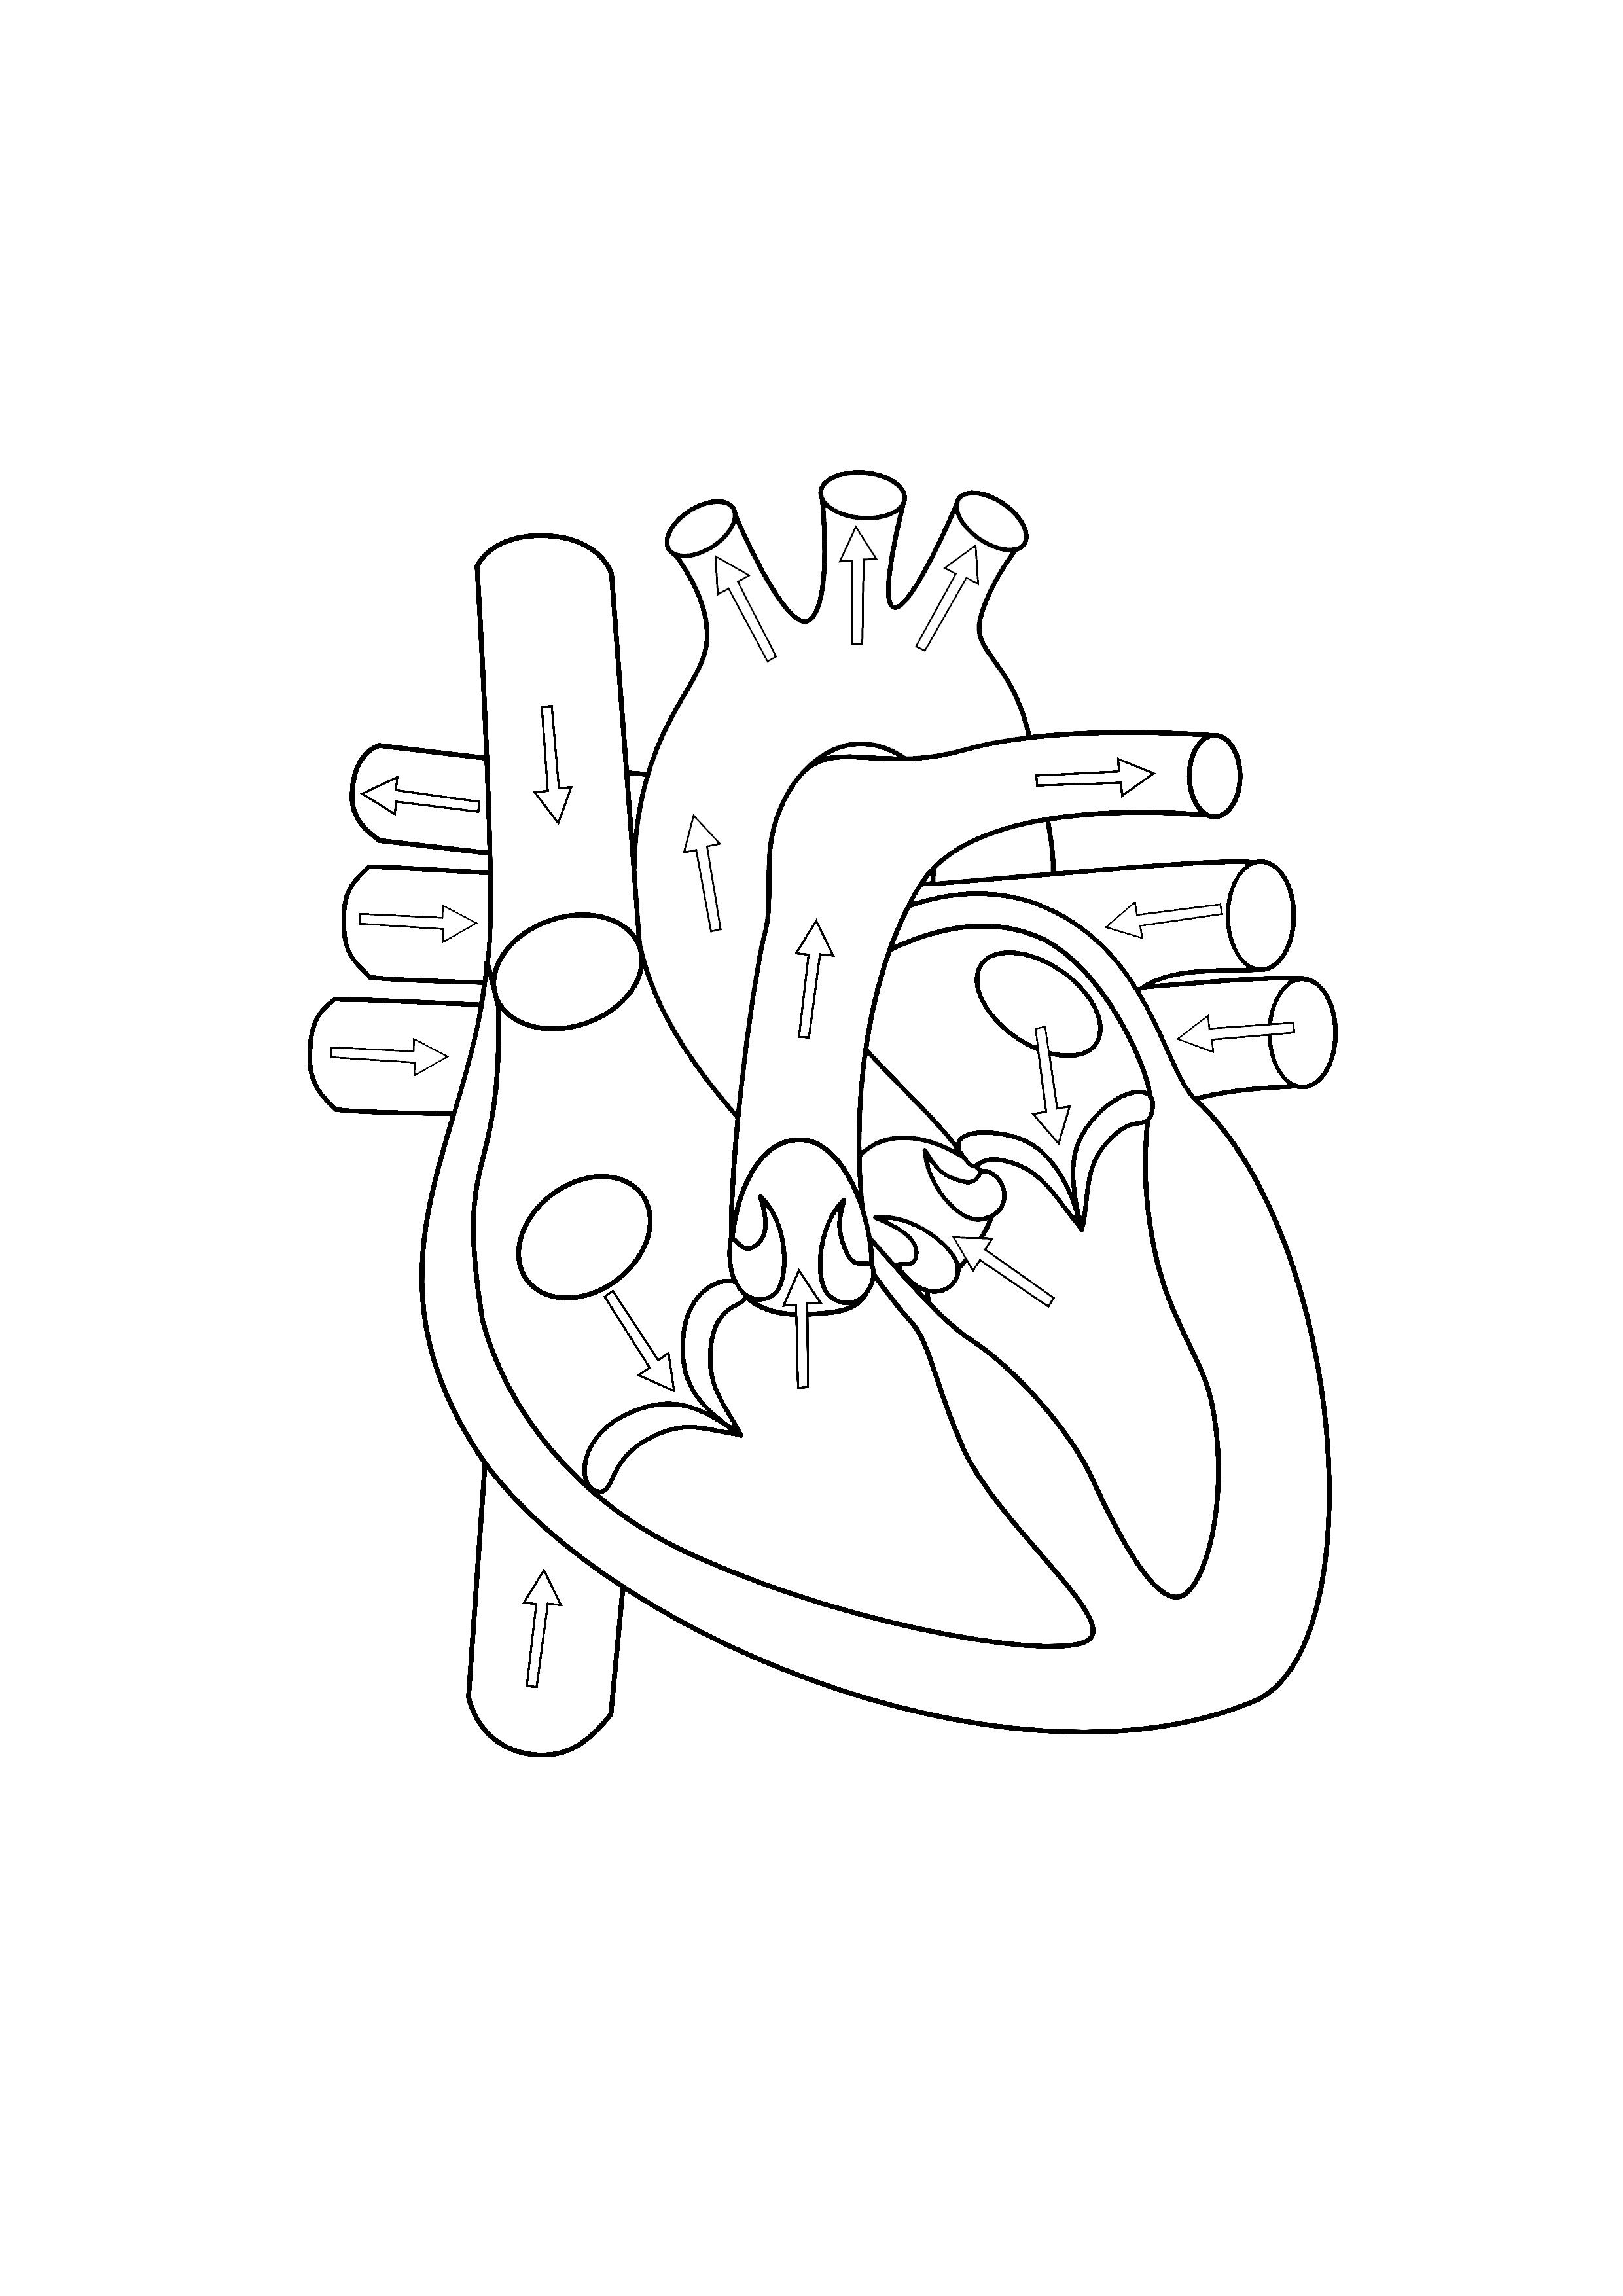

921x690 Anatomical Heart Coloring Pages

620x875 Anatomy Coloring Pages Heart

2550x3300 Anatomical Heart Coloring Page

608x786 Anatomy Of The Heart Coloring Pages Heart Anatomy Coloring Pages

600x848 Healthy Heart In Human Anatomy Coloring Pages Bulk Color

600x450 Heart Anatomy Coloring Pages Heart Anatomy Coloring Pages